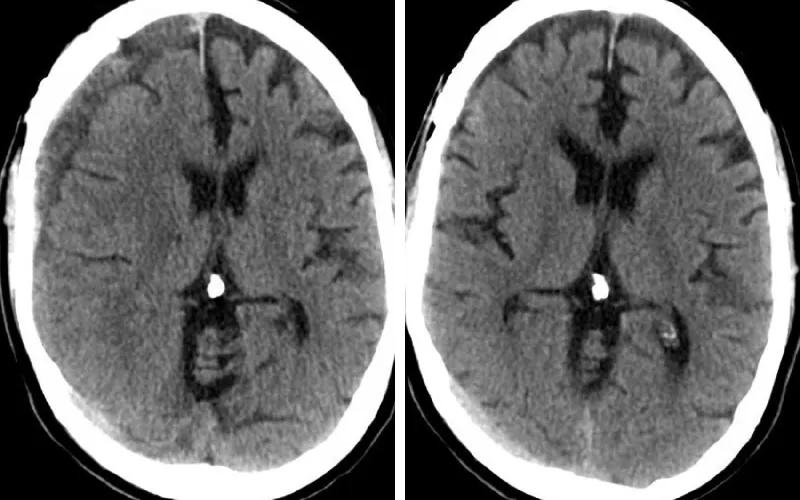

Subdural hematoma

(L) Right subacute subdural hematoma; (R) Resolution of subdural hematoma after MMA embolization.